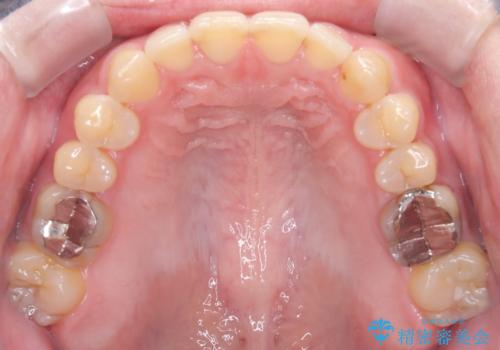

- 前歯の咬み合わせが気になるとのことで来院されました。

前歯が噛んでいない状態(開咬)のため、インビザライン矯正で改善することとしました。

前歯が嚙んでない場合(開咬)、顎間ゴムというゴムを使用してもらうことがあります。顎間ゴムは、前歯を噛み合わせるための力を与える補助的な役割があります。

マウスピース矯正は、患者様のご協力が重要です。マウスピースをきちんと装着し、歯科医院での定期検診が必要になります。